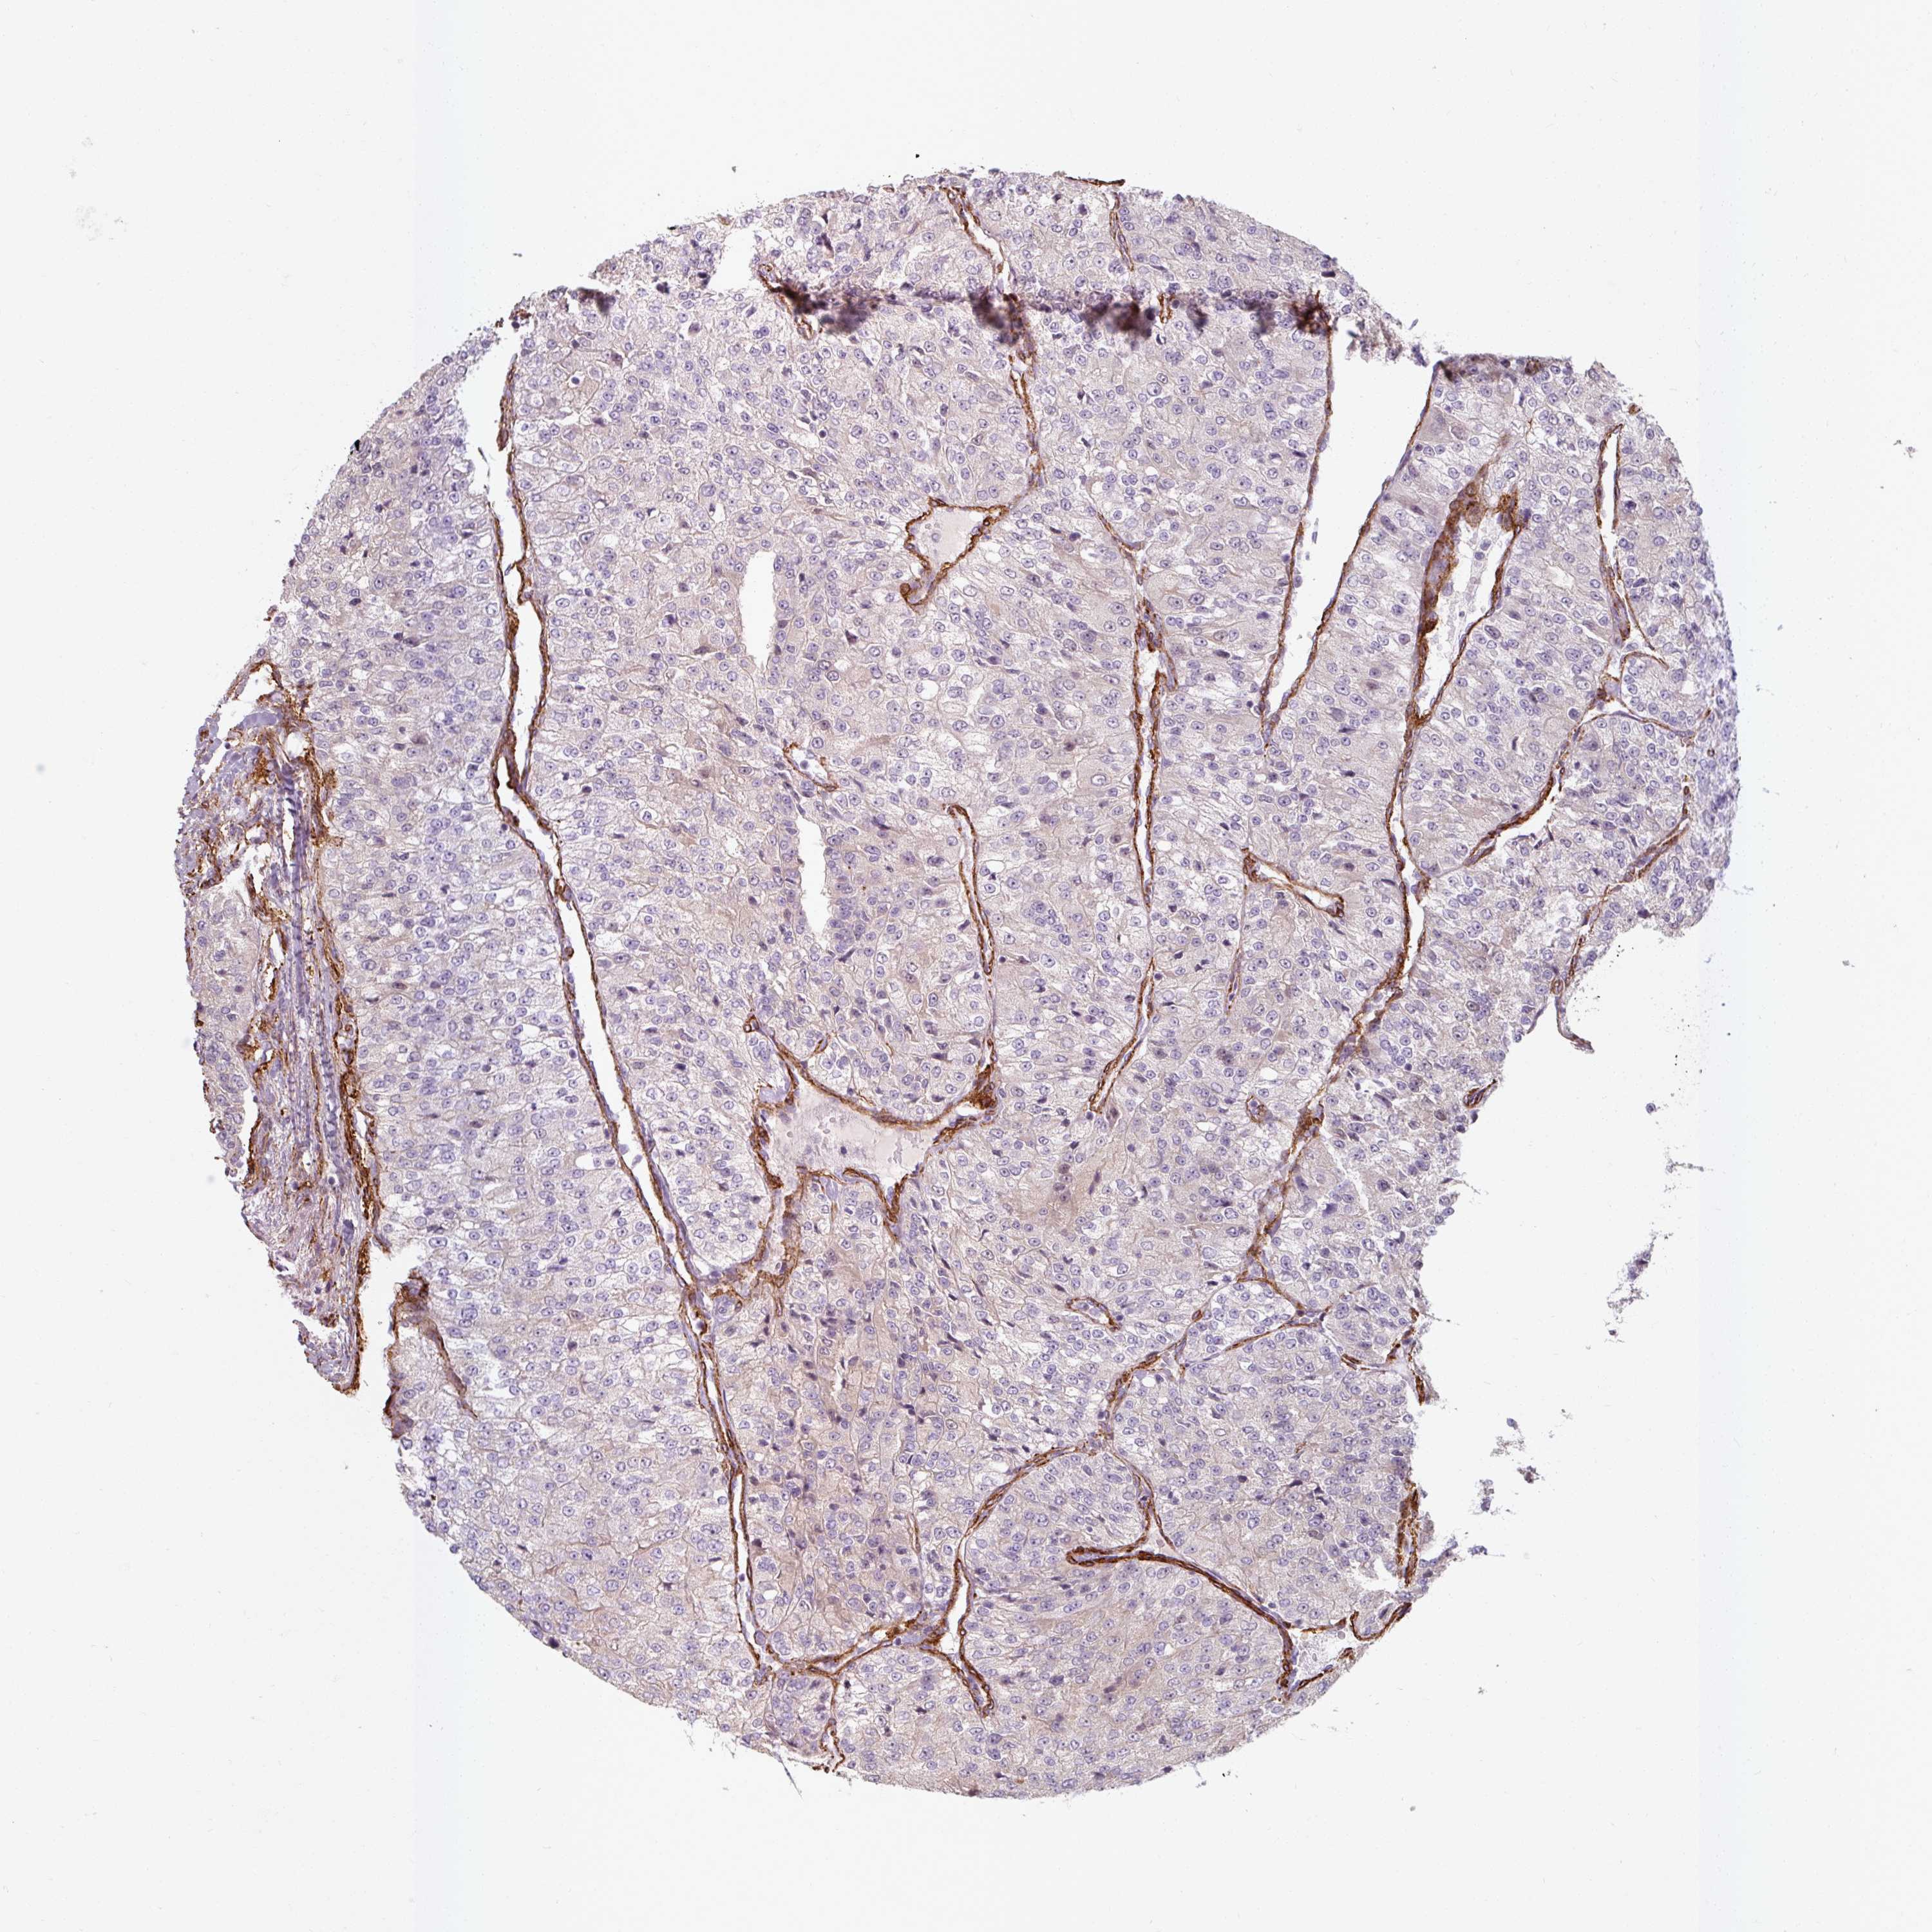

KIDNEY RENAL CLEAR CELL CARCINOMA (VALIDATION) - Interactive survival scatter ploti

The Survival Scatter plot shows the clinical status (i.e. dead or alive) for all individuals in the patient cohort, based on the same data that underlies the corresponding Kaplan-Meier plots. Patients that are alive at last time for follow-up are shown in blue and patients who have died during the study are shown in red.

The x-axis shows the expression levels (FPKM) of the investigated gene in the tumor tissue at the time of diagnosis. The y-axis shows the follow-up time after diagnosis (years). Both axes are complimented with kernel density curves demonstrating the data density over the axes. The top density plot shows the expression levels (FPKM) distribution among dead (red) and alive patients (blue). The right density plot shows the data density of the survived years of dead patients with high and low expression levels respectively, stratified using the cutoff indicated by the vertical dashed line through the Survival Scatter plot. This cutoff is automatically defined based on the FPKM cutoff that minimizes the p-score. The cutoff can be changed by dragging the vertical line or by entering a cutoff value in the square labeled "Current cut-off".

Under the Survival Scatter plot the p-score landscape (black curve; left axis) is shown together with dead median separation (red curve; right axis). Dead median separation is the difference in median mRNA expression between patients who have died with high and low expression, respectively. It is calculated as follows: median FPKM expression of dead patients with high expression - median FPKM expression of dead patients with low expression. This is intended to aid the user in visually exploring custom cutoffs and the associated p-scores and dead median separation.

Individual patient data is displayed and can be filtered by clicking on one or more of the category buttons on the top of the page. Categories describing expression level and patient information include: high, low, alive, dead, female, male and tumor stages. The scale of the x-axis can be toggled between linear and log-scale by clicking on the "x log" button. Mouse-over function shows TCGA ID, patient information and mRNA expression (FPKM) for each patient.

& Survival analysisi

Kaplan-Meier plots summarize results from analysis of correlation between mRNA expression level and patient survival. Patients were divided based on level of expression into one of the two groups "low" (under cut off) or "high" (over cut off). X-axis shows time for survival (years) and y-axis shows the probability of survival, where 1.0 corresponds to 100 percent.

MRPS5 is not prognostic in Kidney Renal Clear Cell Carcinoma (validation)

Best expression cut offi

Based on the FPKM value of each gene, patients were classified into two groups and association between prognosis (survival) and gene expression (FPKM) was examined. The best expression cut-off refers the FPKM value that yields maximal difference with regard to survival between the two groups at the lowest log-rank P-value. Best expression cut-off was selected based on survival analysis .

When clicking on this number, the vertical dashed line indicating cut-off, the interactive survival plot, and the Kaplan-Meier curve will be adjusted to show results based on the best expression cut-off.

: 7.26

TCGA RNA samplesi

RNA-seq data is reported as average FPKM (number Fragments Per Kilobase of exon per Million reads), generated by the The Cancer Genome Atlas (TCGA) .

Normal distribution across the dataset is visualized with box plots, shown as median and 25th and 75th percentiles. Points are displayed as outliers if they are above or below 1.5 times the interquartile range. FPKM values of the individual samples are presented next to the box plot.

Average pTPM 7.0

Number of samples 100